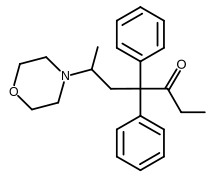

Open chain opioids

Amidones

- Dextromethadone

- Dipipanone

- Isomethadone=

- Levoisomethadone

- Levomethadone

- Methadone

- Methadone intermediate

- Normethadone

- Norpipanone

- Phenadoxone (heptazone)

Structures